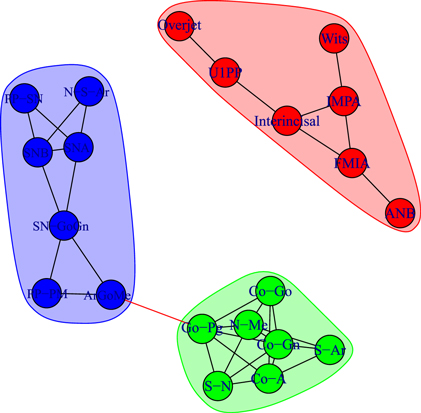

We detect modules by applying the walktrap algorithm [42] on the complete graphs corresponding to consider all the possible edges weighted with their correlation rij; in particular, we use the igraph [44] implementation of the function walktrap.community of R [45]. To compare the results with the empirical outcomes of section 3.1, we show in all the pictures only links with a correlation correlation  and only nodes connected by such links. The analysis of the modules shows interesting differences among the three groups of patients: in fact, the modules characterising the networks of the patients before control (T1) and the untreated control patients (U2) share a similar structure (see figures 6 and 8) with three modules composed by analogous nodes. In fact, like in figure 3, the modules of T1 shown in figure 6 correspond to dentoalveolar adaptive nodes (top right of the picture), to skeletal horizontal nodes (bottom right of the picture) and skeletal vertical nodes (left of the picture); a similar correspondence exists among figures 5 and 8. Notice that for both T1 and U2 the modules are either separated or linked by negative links, indicating that such groups of nodes work as separate, non interacting, oro-facial modules. On the other hand, the network of treated patients (T2, figure 7) shows more modules ; apart to the new (respect to T1 and U2) isolated community formed by overjet and overbite (whose correlation is due to the successful action of the braces), the remaining communities are much more interlinked, possibly hinting a harmonization of the orofacial modules that start working together thanks to the orthodontic correction.

and only nodes connected by such links. The analysis of the modules shows interesting differences among the three groups of patients: in fact, the modules characterising the networks of the patients before control (T1) and the untreated control patients (U2) share a similar structure (see figures 6 and 8) with three modules composed by analogous nodes. In fact, like in figure 3, the modules of T1 shown in figure 6 correspond to dentoalveolar adaptive nodes (top right of the picture), to skeletal horizontal nodes (bottom right of the picture) and skeletal vertical nodes (left of the picture); a similar correspondence exists among figures 5 and 8. Notice that for both T1 and U2 the modules are either separated or linked by negative links, indicating that such groups of nodes work as separate, non interacting, oro-facial modules. On the other hand, the network of treated patients (T2, figure 7) shows more modules ; apart to the new (respect to T1 and U2) isolated community formed by overjet and overbite (whose correlation is due to the successful action of the braces), the remaining communities are much more interlinked, possibly hinting a harmonization of the orofacial modules that start working together thanks to the orthodontic correction.

Figure 6. Module repartition of the Class III patients before treatment (T1). The detected modules correspond to dentoalveolar adaptive nodes (top right—red), to skeletal horizontal nodes (bottom right—green) and skeletal vertical nodes (left—blue).

Standard image High-resolution imageFigure 7. Module repartition of the Class III patients after comprehensive treatment (T2). Apart from the isolated community corresponding to the treatment-induced overjet–overbite correlation, the four modules are inter-connected.

Standard image High-resolution imageFigure 8. Module repartition of the Class III control subjects (U2). As in figure 6, the detected modules correspond to dentoalveolar adaptive nodes (top right—red), to skeletal horizontal nodes (bottom right—green) and skeletal vertical nodes (bottom left—blue).

Standard image High-resolution imageHence, the arrangement of modules of at the start (T1, figure 6) and at the end of treatment (T2, figure 7) of the same Class III patients confirms the strict interlinked module topology after RME/FM treatment, as compared with untreated controls (U2, figure 8).